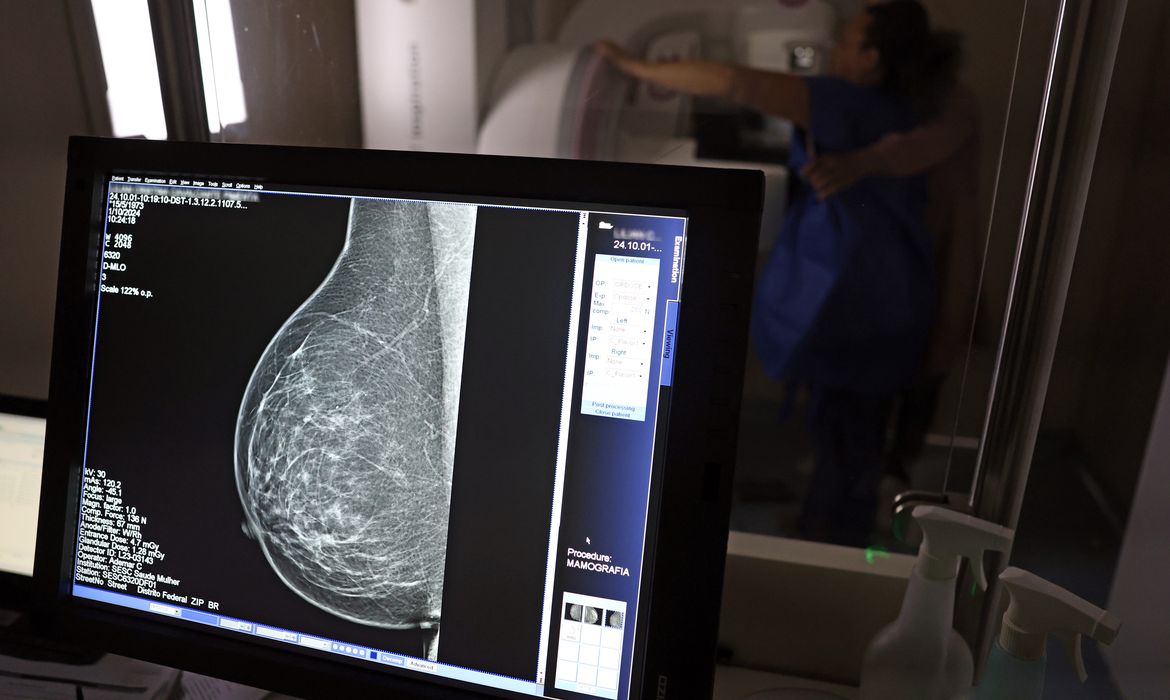

Câncer de mama: uma em cada três pacientes tem menos de 50 anos

Dados do Painel Oncologia Brasil, analisados pelo Colégio Brasileiro de Radiologia e Diagnóstico por Imagem (CBR), indicam que mais de 108 mil mulheres com menos de 50 anos foram diagnosticadas com câncer de mama no Brasil no período entre 2018 e 2023 – uma média de uma em três mulheres diagnosticadas com a doença.

Para a entidade, os números reforçam a importância de ampliar o rastreamento do câncer de mama por meio da realização de mamografia em mulheres abaixo dos 50 anos e acima dos 70 anos, faixas etárias que não estão incluídas na recomendação padrão de exames preventivos no âmbito do Sistema Único de Saúde (SUS).

O levantamento mostra que, entre janeiro de 2018 e dezembro de 2023, o Brasil registrou mais de 319 mil diagnósticos de câncer de mama, sendo 157,4 mil em mulheres de 50 a 69 anos, faixa etária atualmente recomendada para o rastreamento.

Entre mulheres com idade entre 40 e 49 anos, foram registrados 71.204 casos de câncer de mama, enquanto 19.576 mulheres com idade entre 35 e 39 anos também receberam o diagnóstico da doença. Juntas, ambas as ocorrências representam 33% do total de casos diagnosticados no período.

Já entre mulheres acima de 70 anos, foram identificados 53.240 casos de câncer de mama.

O CBR alerta ainda para o crescimento do total de casos de câncer de mama no país – em 2018, foram registrados 40.953 diagnósticos, contra 65.283 em 2023, um aumento de 59% em seis anos.

Os dados revelam ainda um total de 173.690 mortes por câncer de mama no país entre 2018 e 2023. O número de óbitos passou de 14.622 em 2014 para 20.165 em 2023 – um aumento de 38% nesse período.

Os números também mostram que 38.793 mulheres com menos de 50 anos morreram de câncer de mama, o que corresponde a 22% do total de óbitos no período. Entre as mulheres acima de 70 anos, foram registradas 56.193 mortes (32% do total).

O rastreamento precoce, de acordo com o CBR e com base em relatos de especialistas, pode reduzir em até 30% a mortalidade por câncer de mama. “Isso significa que metade das vidas perdidas para a doença poderia ser salva com um diagnóstico no momento certo”, reforçou o colégio.